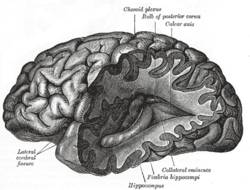

Neuroimaging or brain imaging is the use of various techniques to either directly or indirectly image the structure, function/pharmacology of the nervous system. It is a relatively new discipline within medicine, neuroscience, and psychology.[1] Physicians who specialize in the performance and interpretation of neuroimaging in the clinical setting are neuroradiologists.

Neuroimaging falls into two broad categories:

- Structural imaging, which deals with the structure of the nervous system and the diagnosis of gross (large scale) intracranial disease (such as tumor), and injury, and

- Functional imaging, which is used to diagnose metabolic diseases and lesions on a finer scale (such as Alzheimer's disease) and also for neurological and cognitive psychology research and building brain-computer interfaces.